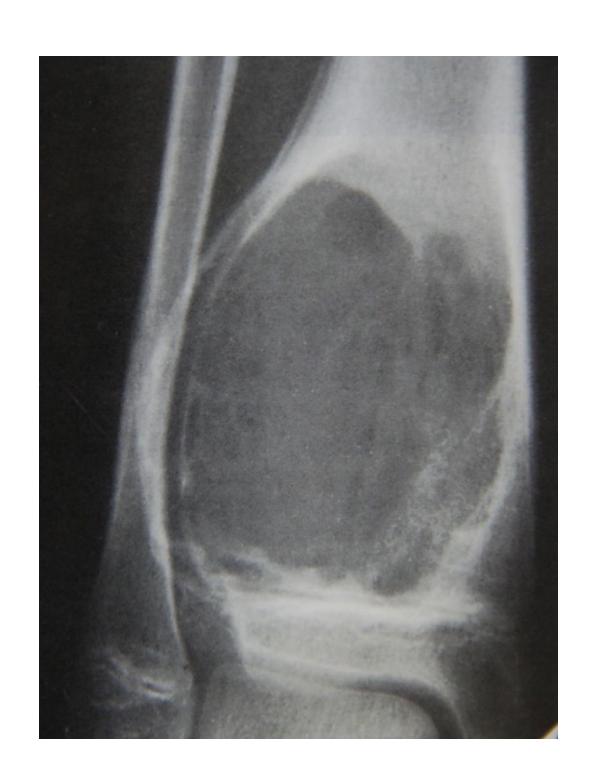

Clinical Cases:

-

14-year-old patient with pain and swelling at lower right thigh

- Most important X-ray findings: Sun ray appearance, Codmanโs triangle

- Diagnosis: Osteosarcoma

14-year-old patient complaining of pain and swelling at lower R thigh

- Findings: Codmanโs triangle, Sun burst appearance

Codman trinagle